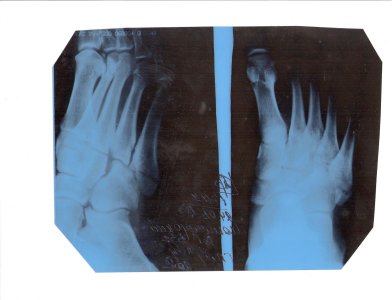

Здравствуйте! 2 недели назад неудачно прыгнул и сломал пятую плюсневую кость левой ноги у основания, носил "сапожок" все это время и передвигался на костылях, сегодня сделал повторный снимок и врач снял гипс и сказал что жесткого эластичного бинта достаточно, ничего не болит, наступать без гипса не хочу, через 10-12 дней опять на проверку и через это же время можно будет ходить с тросточкой. Стоит ли обращаться к другому врачу или все нормально и метод лечения вполне адекватный? Прикреплю снимки. Посмотреть вложение 12575 Посмотреть вложение 12576

Картинка низкого качества, линию перелома не вижу, "угадывается" что то типа Джонса Тактик лечения много, можно и так, как вы пишите Ничего не могу сказать Покажите нормальную картинку